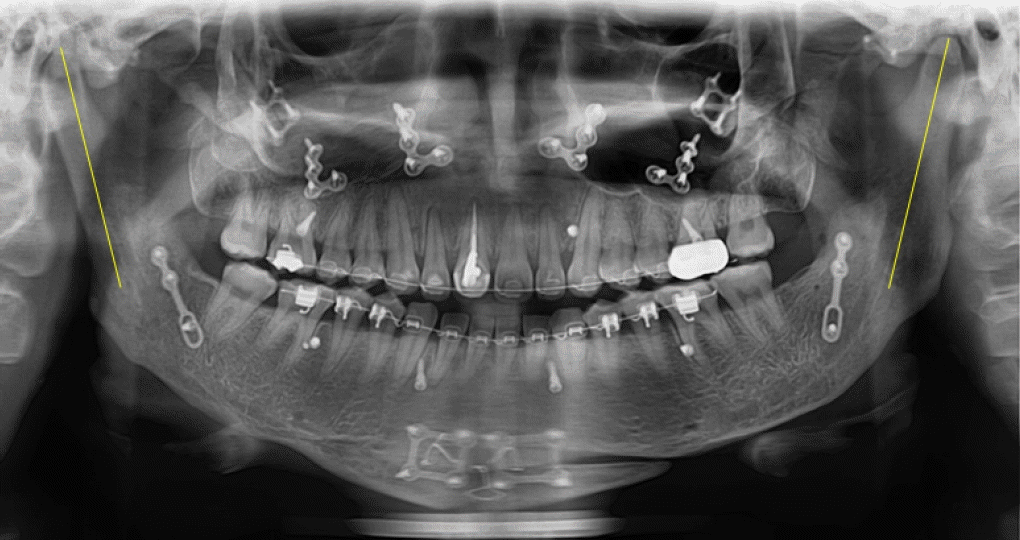

28세 여성이 안면비대칭과 턱관절의 불편감으로 내원하였다. 안모는 우측으로 비대칭이 관찰되었으며, 우측 턱관절부위의 관절잡음이 있었으며 26mm 개구 시 과두걸림이 있었다. 최대개구량은 48mm이고 우측으로 변위된 개구 양상을 보였다. 안면 CT와 X-ray 촬영 결과, 좌측 하악지가 우측 하악지에 비해 12.89mm 길었으며 관절까지의 방향이 우측 하악지에 비해 외측으로 향해 있는 것을 알 수 있었다(Fig. 1). 우측 하악체의 길이가 좌측에 비해 길고 이로 인해 하악 턱끝은 정중선에 비해 우측으로 13.8mm 편위되어 있었다. 그리고 교합평면은 좌측으로 기울어지고 구치부 반대교합과 전치부 절단교합이 존재하였다(Fig. 2). 안면비대칭과 턱관절원판의 정복성 전방변위로 진단하고 하악골의 비대칭과 교합평면의 개선을 위해 턱교정수술과 치아교정술을 계획하였다. 턱교정수술은 상악골 후상방(좌측: 3.5mm, 우측: 4.5mm)이동하고, 하악골은 후방(좌측: 17.5mm, 우측: 5.5mm) 이동하였다(Fig. 3). 턱끝성형술과 하악골 윤곽성형술을 통해 하악골과 안모의 대칭에 도움을 주었다. 하악골수술은 시 시상분할절골술을 이용하였으며, 관절과두가 포함된 근심골편을 재위치시켜주어 과두걸림을 해소하려 하였다. 수술 2주후 치아교정술을 시작하면서 개구연습을 진행하였으며 비대칭적 개구 습관의 교정을 위해 탄성고무줄을 이용하여 중심선에 맞게 진행하였다. 수술 6개월 후 평가 시, 안모의 비대칭은 개선된 결과를 보였으며(Fig. 4) 턱관절 부위의 과두걸림은 관찰되지 않고 정상범위 내의 개구 양상을 보였다.- 증례 2

Figure 1.

A. 3D facial CT (frontal view). B. 3D facial CT (submentovertex view). C. Panoramic radiograph.